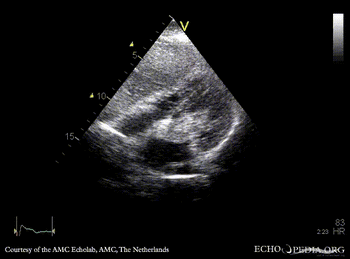

Giant myxoma in left atrium

A2CH